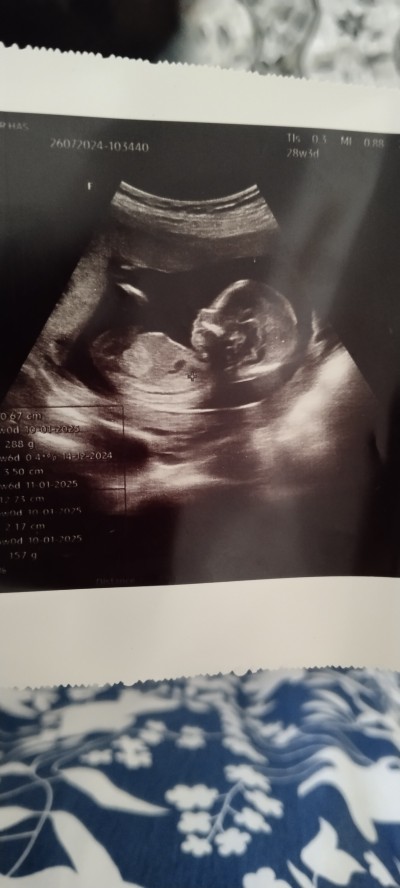

Kızlar cinsiyet tahmini yapar mısınız devlete gidiyorum doktor henüz söylemedi

Gebelik haftası 16

Bacağının olduğu kısımda pipiye benzer bişey gördüm ben aslında ama emin olamadım :) hayırlısı olsun inşallah

Bebek bayağı büyük duruyor görmüştür ama söylememiştir. Benim 16. Haftada devlet ben erkek gördüm demişti yani. Sağlıcakla kucağına alırsın inşallah.

Pipi görünüyor sanki hayırlısı olsn cnm